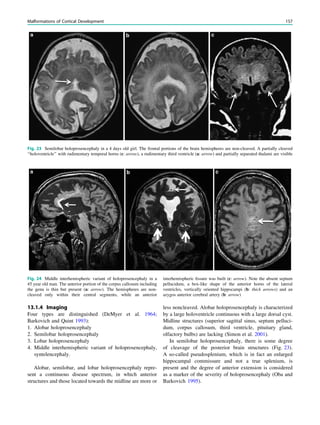

To achieve freedom from seizures following epilepsy

surgery, in some but not all cases not only the epileptogenic

lesion itself but also some perilesional tissue must be

removed. Conceptually, it is the epileptogenic area that has

to be removed, which is defined as cortical area indis-

pensable for the generation of seizures. Practically, it is the